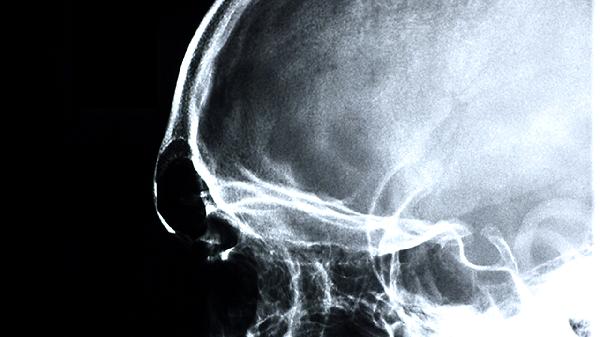

3、脑萎缩

脑萎缩可见于多种神经系统疾病,表现为脑组织体积减小。益智康脑丸可能通过神经营养作用减缓萎缩进程。患者多有情绪改变、运动协调障碍等表现。治疗需结合针对原发病的药物,如甲钴胺片、奥拉西坦胶囊等。